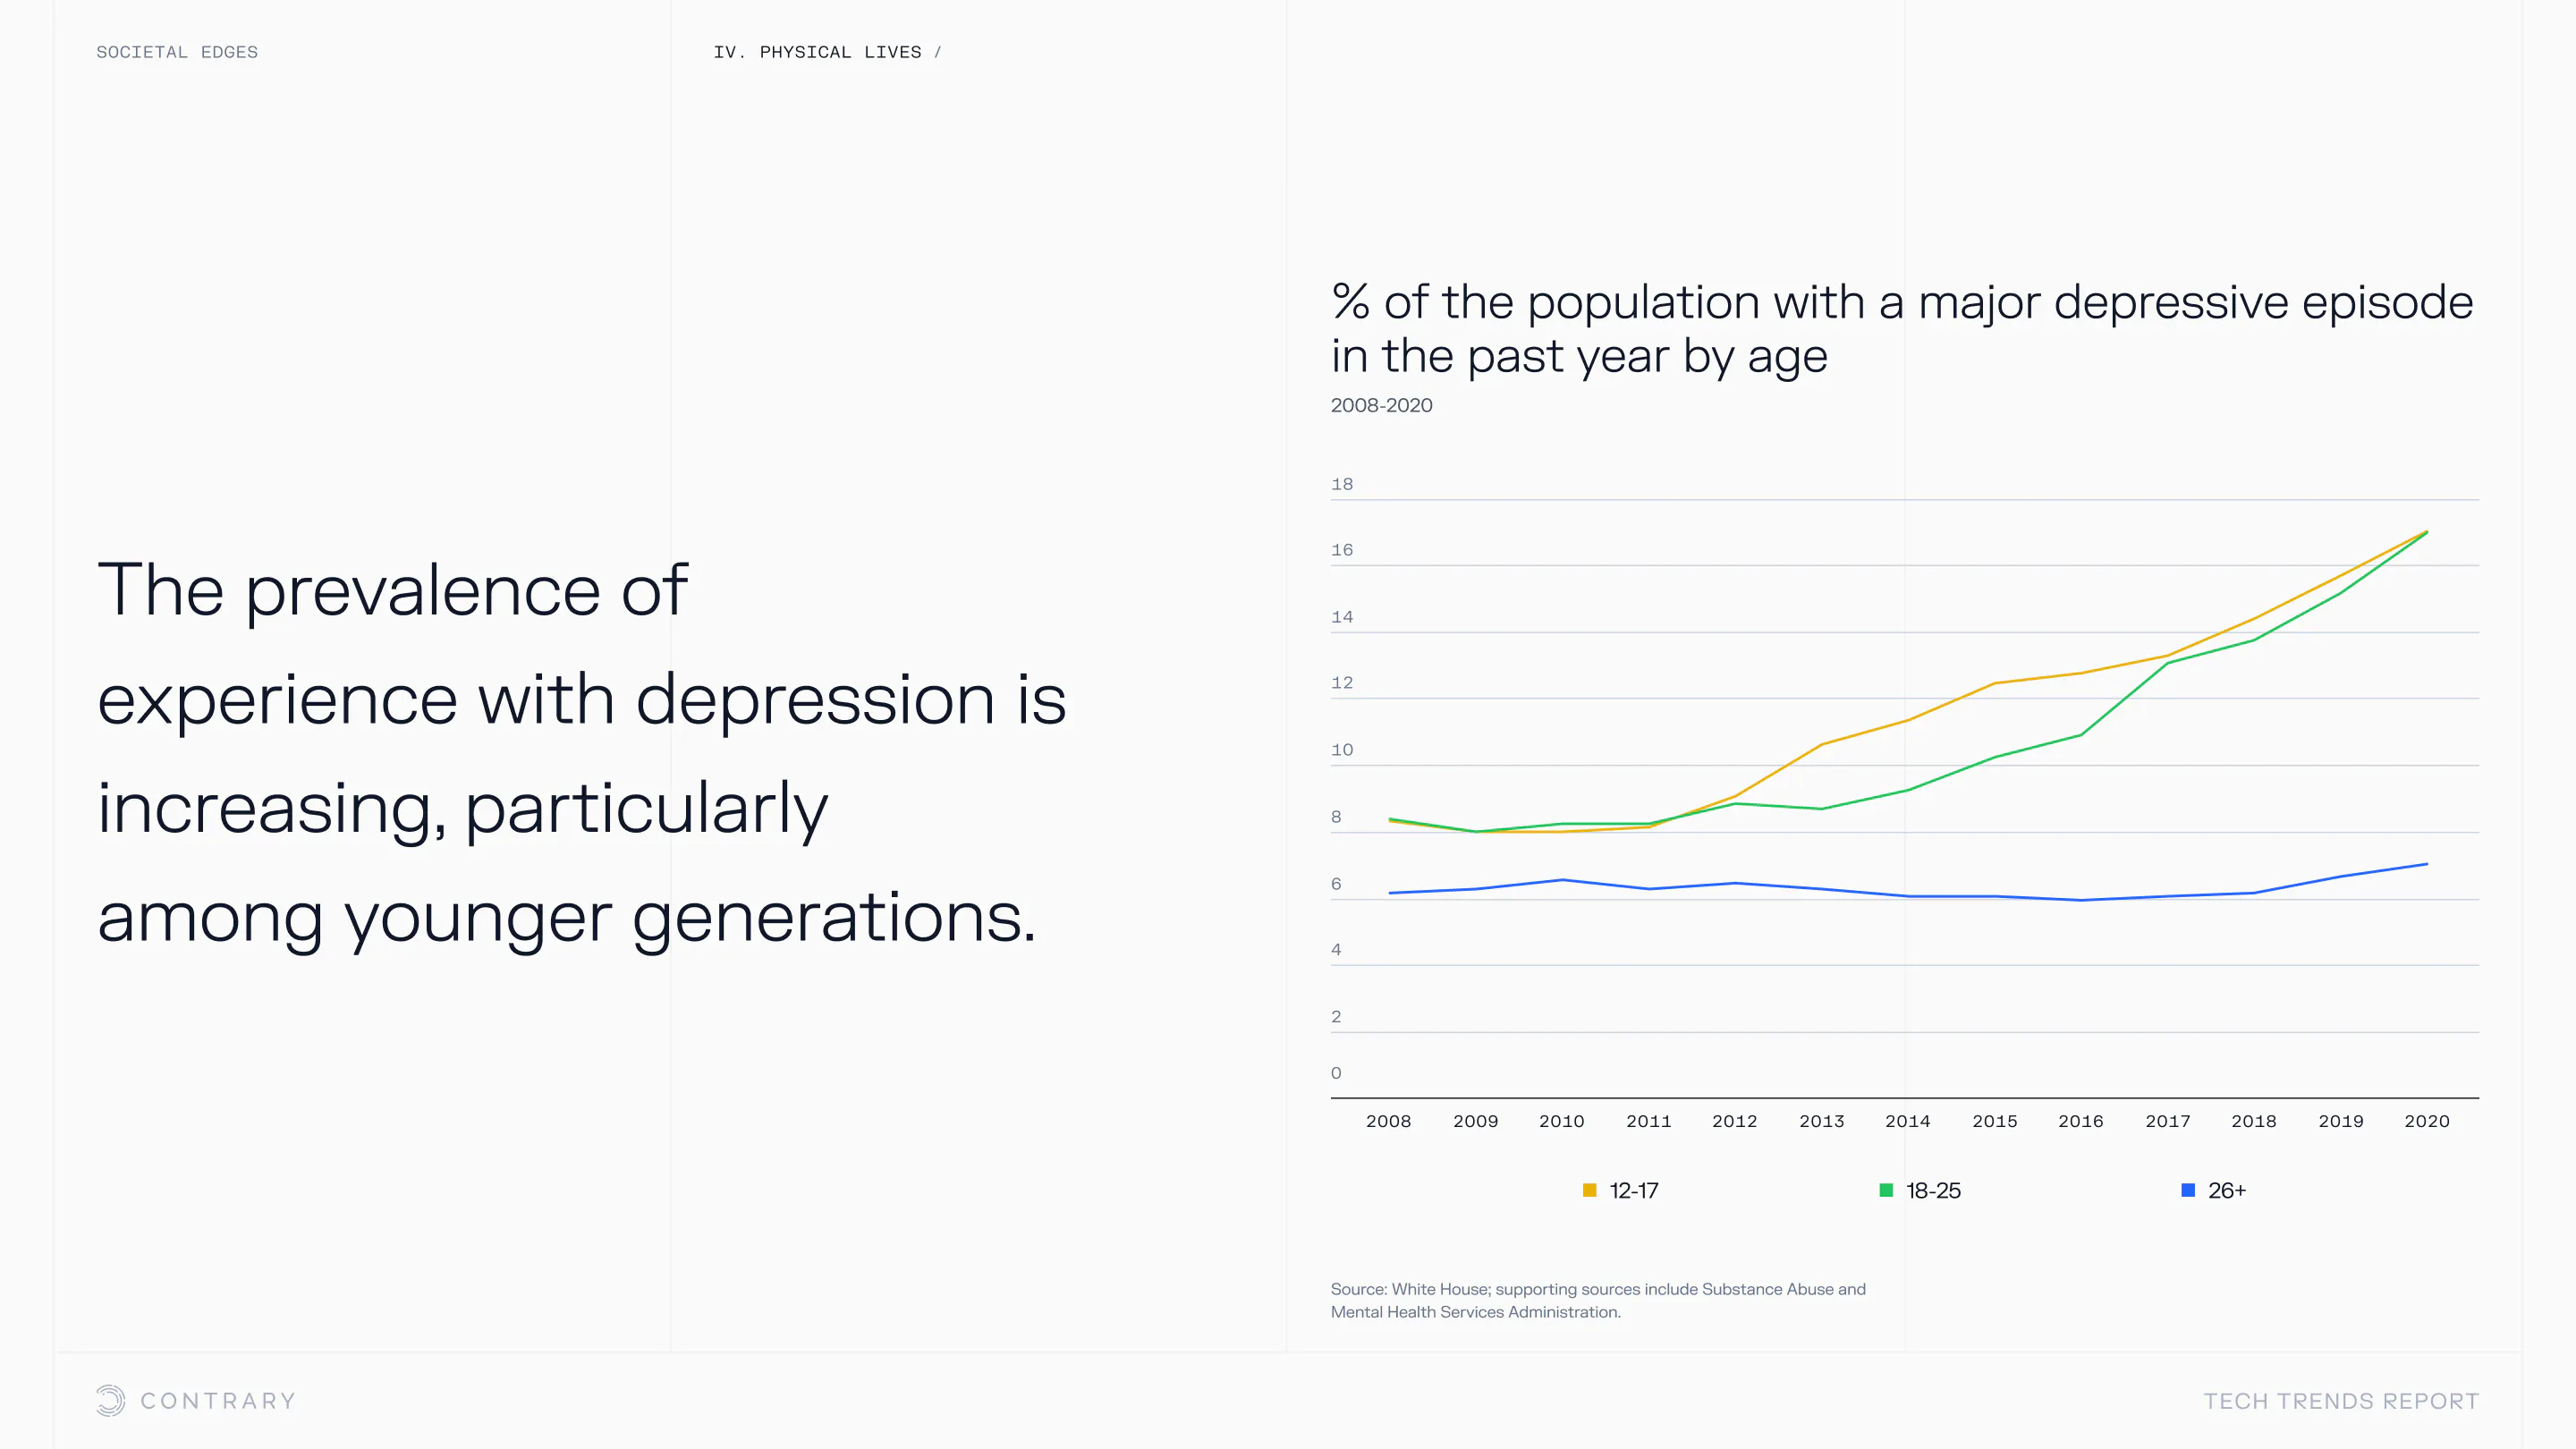

An aging population is bringing up a range of increased concerns, from mental health to disease control. Obesity and gastrointestinal cancers are plaguing younger generations. The cutting edge is tackling a system that has unhealthiness woven into it.